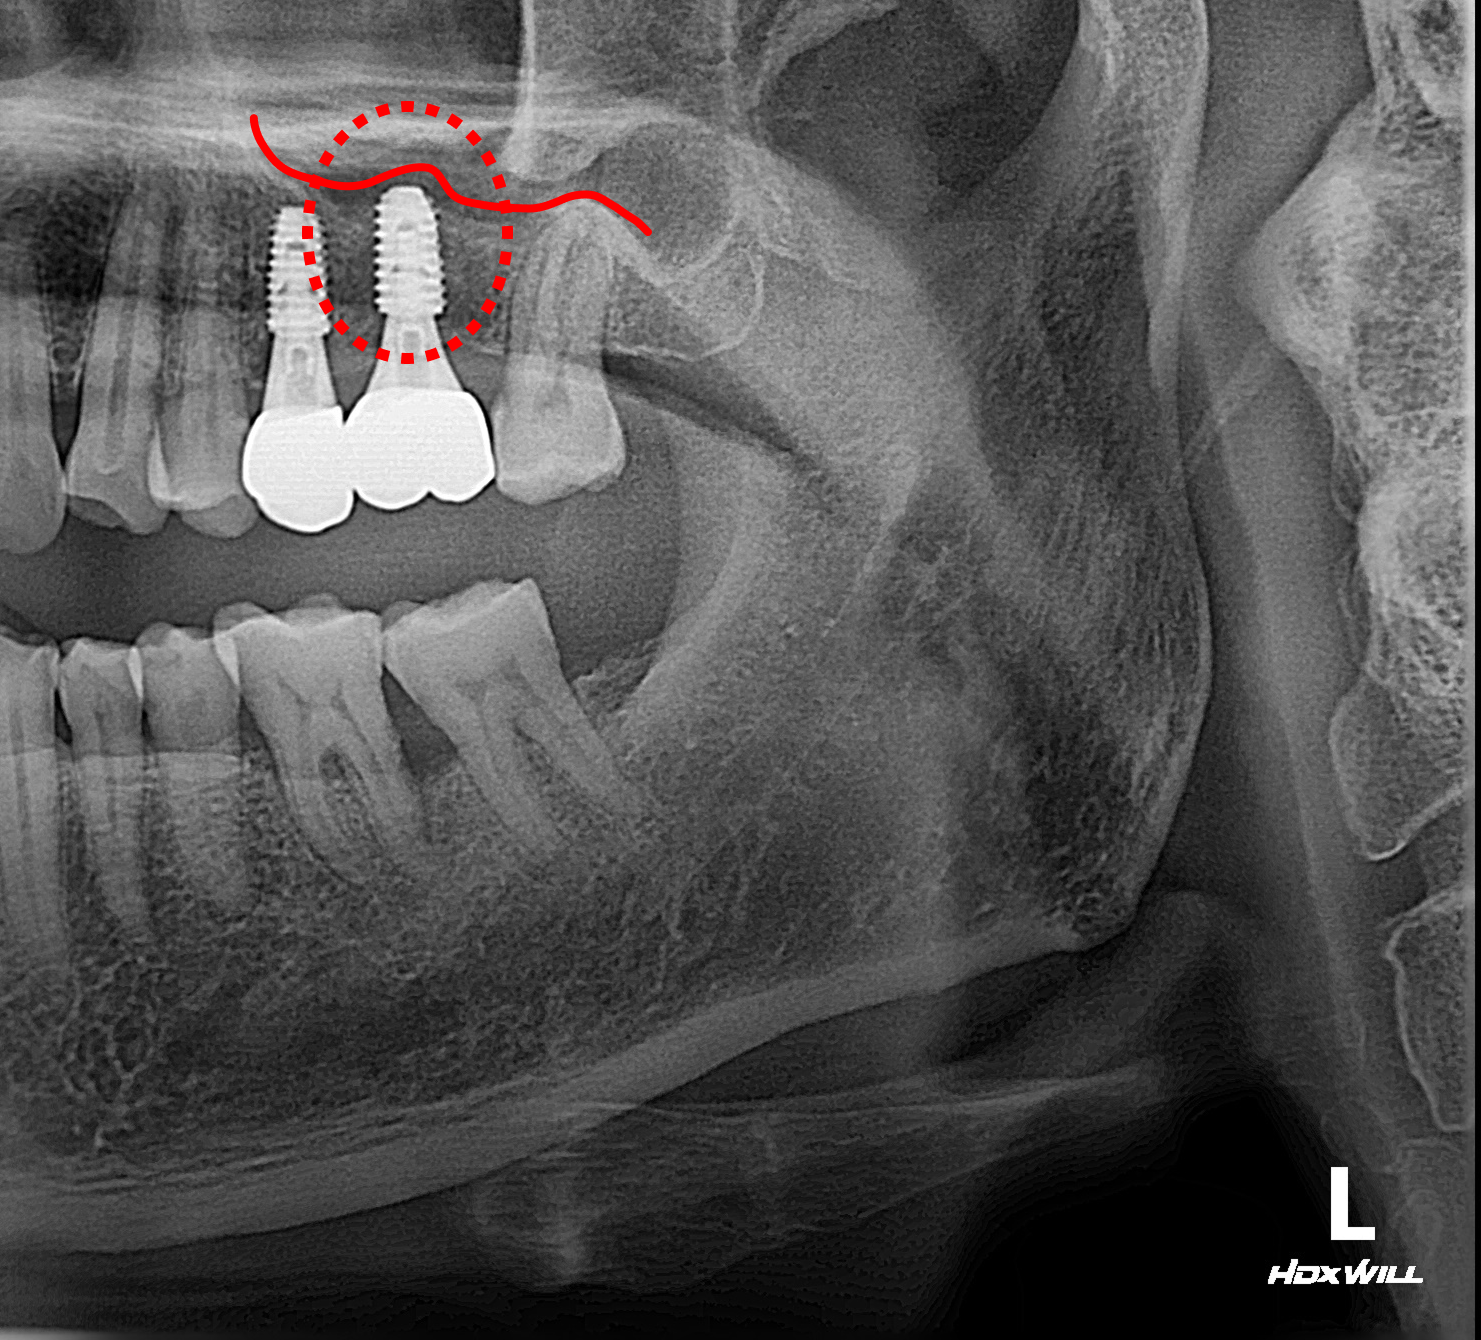

하지만 상악(위턱) 어금니 부위는 해부학적으로 '상악동'이라는 공기 주머니 형태의 빈 공간이 존재하여 본래 잔존골의 두께가 얇은 편입니다. 이에 더해 환자분은 이전의 심한 염증으로 인한 골흡수까지 겹쳐, 임플란트를 지지할 치조골이 절대적으로 부족한 상태였습니다.

안전한 식립 깊이를 확보하기 위해 상악동의 하연 막을 조심스럽게 위로 들어 올리고, 그 하방 공간에 골이식재를 채워 넣는 '상악동 거상술'을 시행했습니다. 수술 시 절개 횟수와 환자의 부담을 줄이기 위해, 거상술 시행과 동시에 임플란트 픽스처(인공 치근) 식립을 병행하여 마무리했습니다.